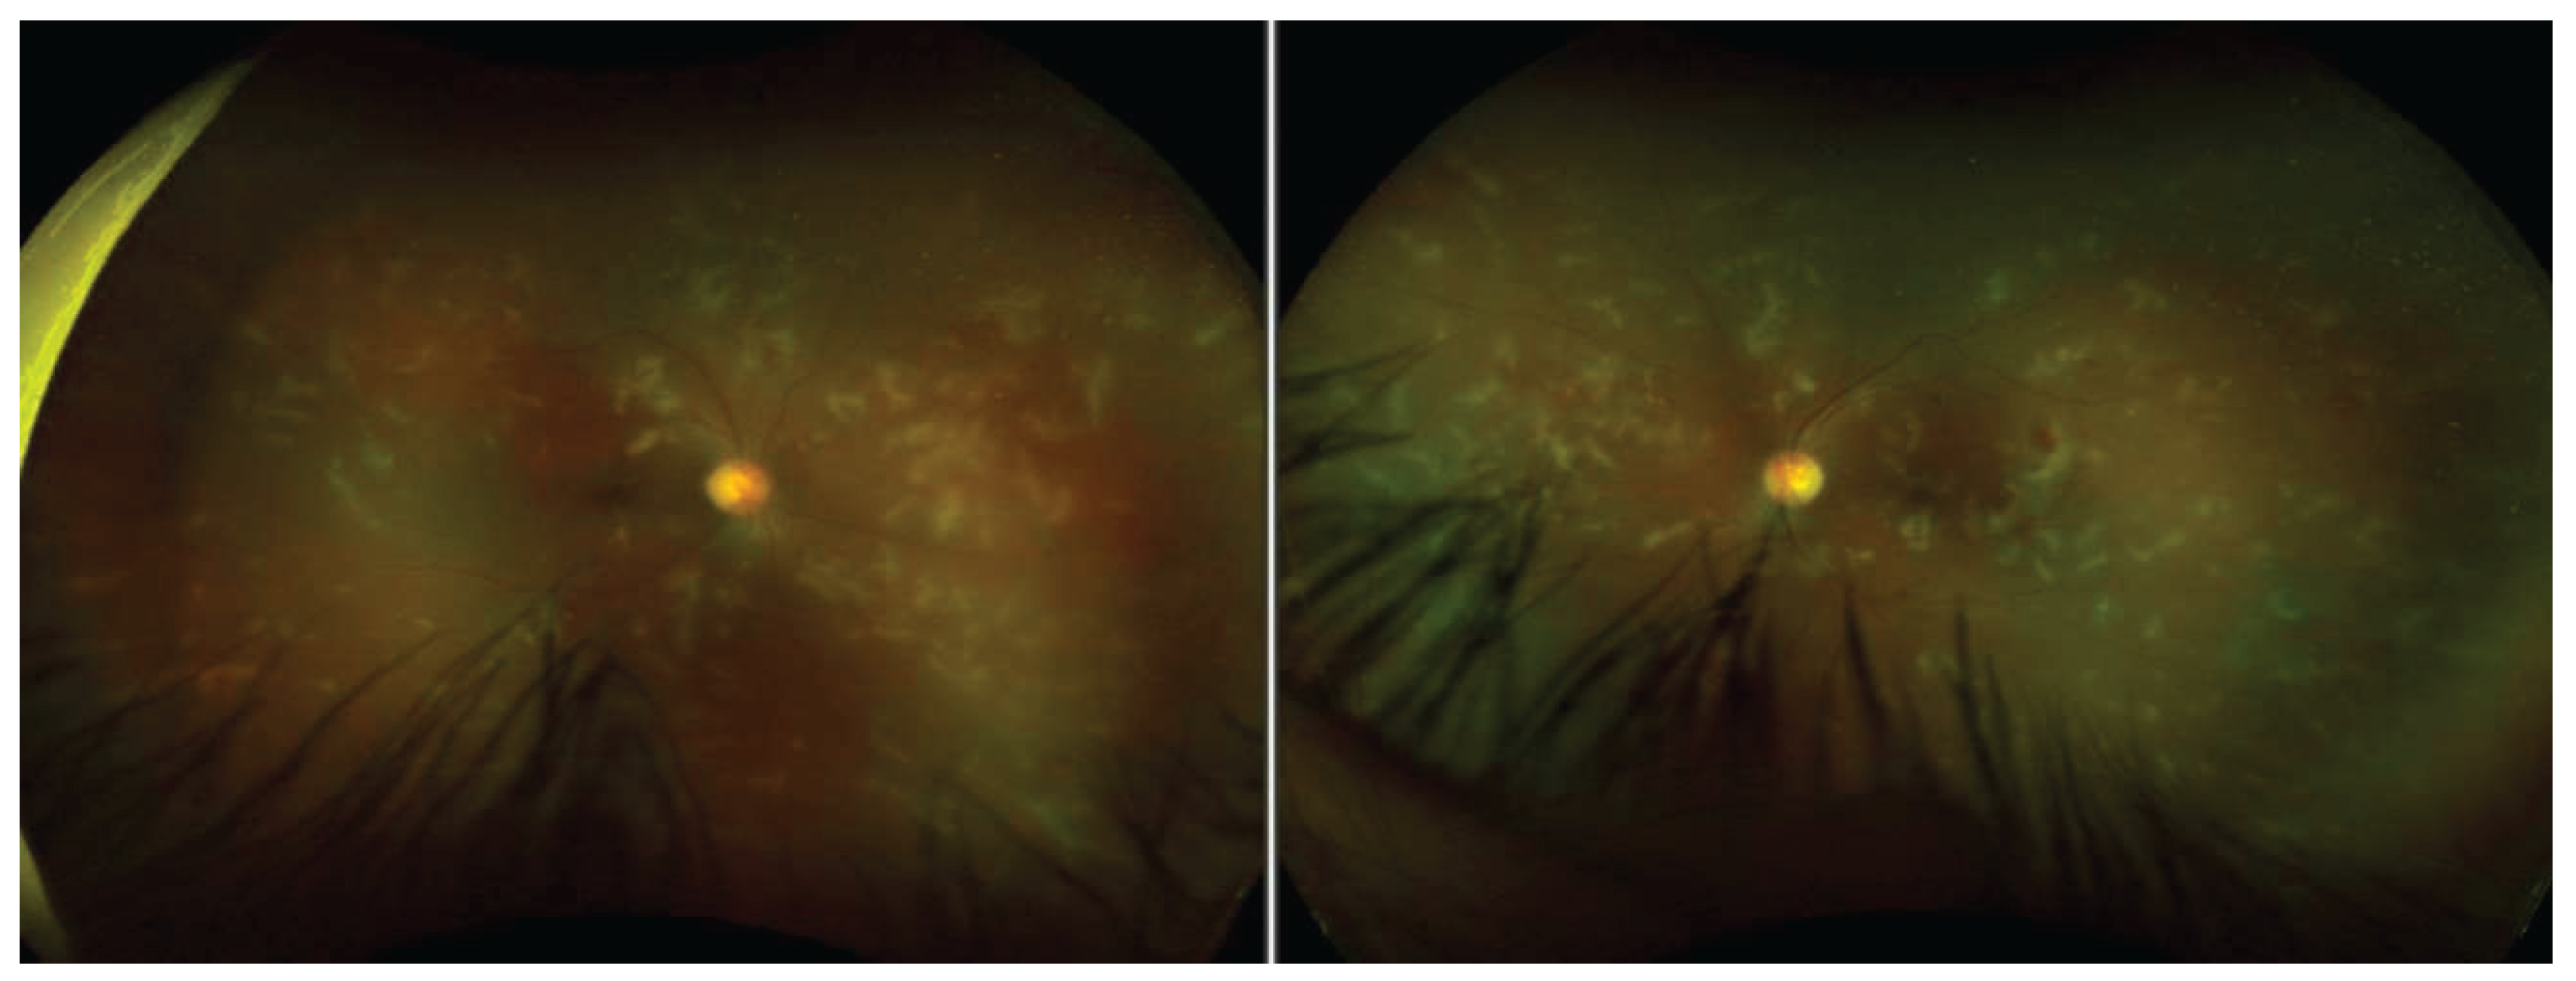

• numerous small hemorrhages and white infiltrates along the retinal vessels and macular edema in both eyes (see Figure 2)

Figure 2. Patient 3, Fundus appearance 3 days postoperatively with small hemorrhages and white infiltrates along the retinal vessels and macular edema in both eyes.